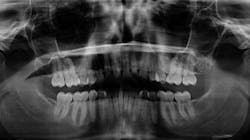

- Did you know that with digital radiographs exposure is minimal and the benefits far outweigh the risks?

I take pride in customizing my established patients’ care to fit their needs. Some of my patients require radiographs every six to 12 months due to their caries risk and lack of home care; others, I recommend they have radiographs every 24 months. Periodontal care is no different; some are on three-month, four-month, and even six-month frequencies. If their needs change, we adapt. Every patient is different, and as such, their needs and treatment must be flexible to reflect that which is in their best interests—without compromising our ability to see to these demands. Again, educating our patients is key.

As it turned out, this young woman was at a very low risk for caries, and we agreed upon a two-year interval for her established care. The question that begs answering is this: what if she wasn’t a low caries risk?